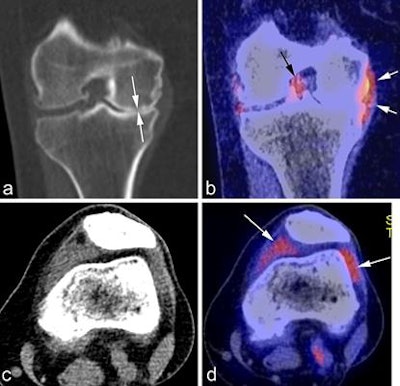

Using F-18 FDG PET can facilitate imaging of active metabolism and visualization of bone turnover changes, and PET can show active synovitis, which has been associated with knee pain in osteoarthritis patients, Hayashi noted. To overcome the major limitations of PET, particularly its relatively low anatomical resolution, use of PET/CT and PET/MR hybrid imaging has been explored, and the feasibility has been demonstrated for assessment of early metabolic or morphologic markers across multiple tissues.

"SPECT/CT is another potential hybrid imaging that can be utilized, and it has been explored recently in the literature," Hayashi said. "But right now these hybrid imaging techniques are not routinely performed in a clinical setting, and available literature evidence is limited. And there are very few studies showing the feasibility of these techniques in osteoarthritis imaging research. For these techniques to be used in clinical practice, there is still a long way to go."